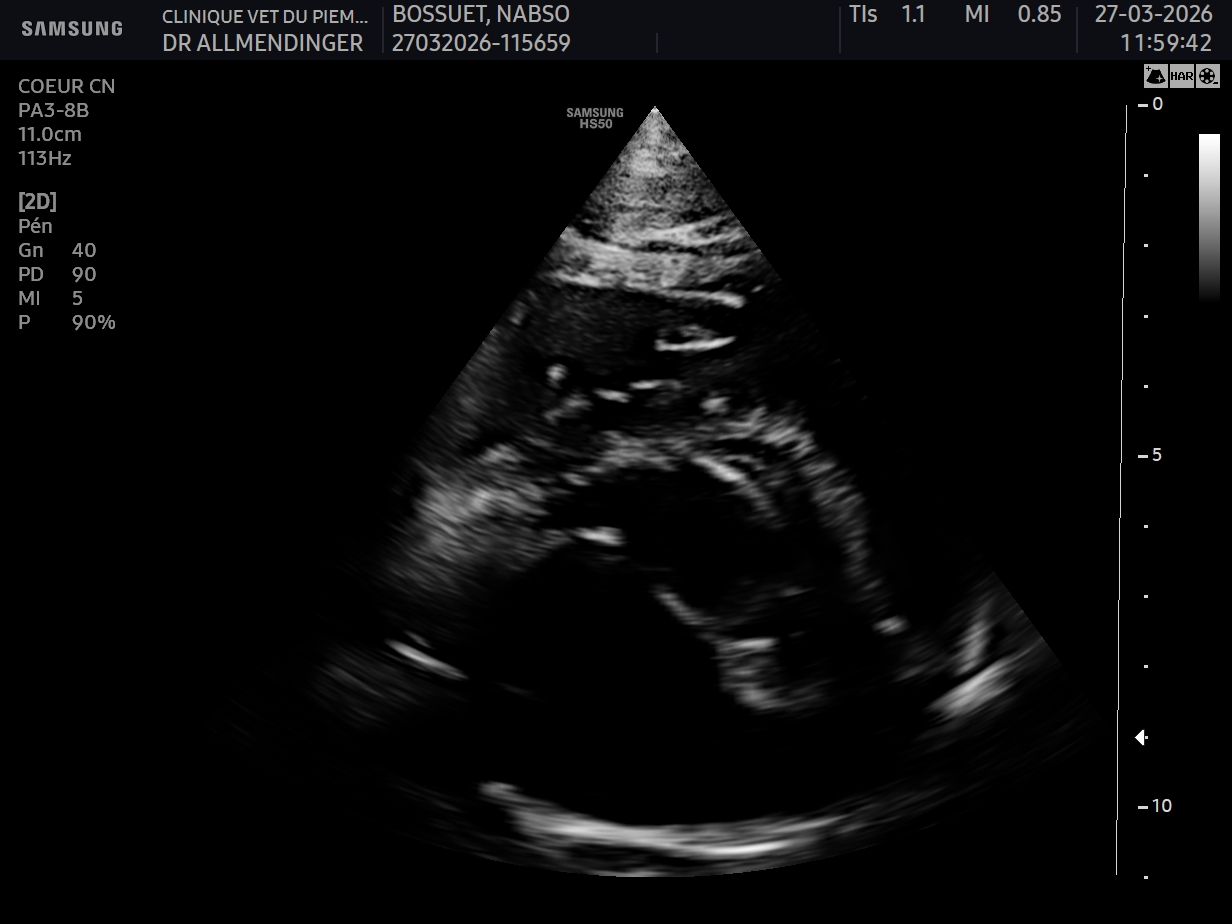

Geste technique : Mesure échographique du LA/Ao (rapport oreillette gauche/aorte)

- Connaître les principaux examens à considérer chez un chien présenté en dyspnée aigue

- Connaître les limites de l’examen échographique pour l’exploration d’une dyspnée aigue chez le chien